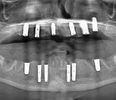

Diş hekimi